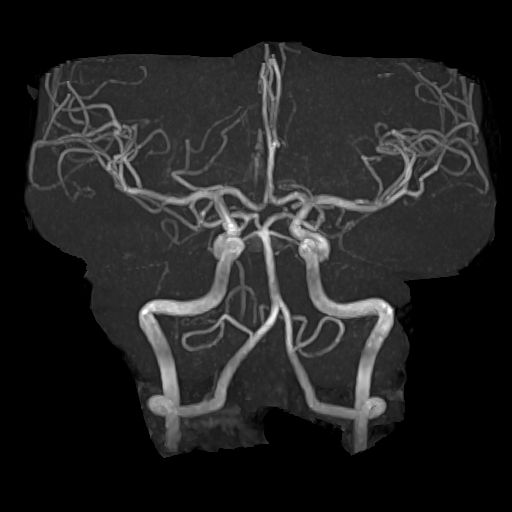

- 脳血管の異常(脳動脈瘤、血管の狭窄など):

脳動脈瘤は破裂するとくも膜下出血を引き起こす危険な病気です。MRIのMRA(MRアンギオグラフィー)という手法を用いることで、脳の血管を立体的に描出し、動脈瘤や血管の狭窄などを早期に発見することが可能です。 - 脳梗塞・脳出血の有無、隠れ脳梗塞の発見: